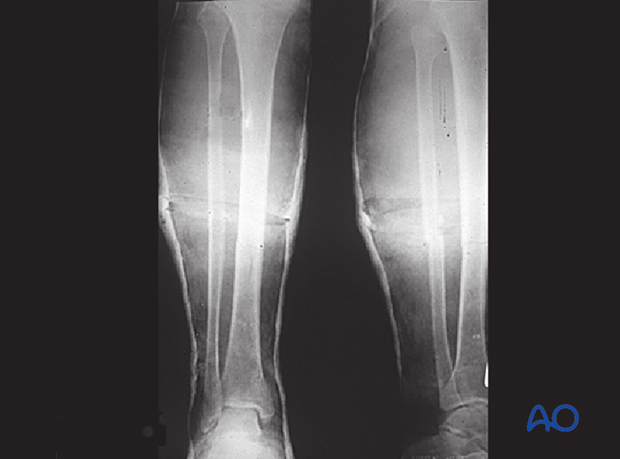

These x-rays show malreduced tibia and fibula fractures in varus and flexion.

To correct the deformity, the original cast had wedges placed laterally and posteriorly. Appropriate alignment was achieved.

These x-rays were taken at 3 months post injury and show appropriate alignment with callus formation along the lateral and posterior cortices of the tibia.

These x-rays show increased bony healing, although incomplete anteriorly.